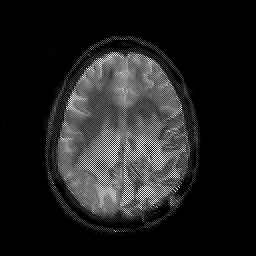

Glioblastoma multiforme overlay -- Slice #36

[Home][Help][Clinical][Tour 1][Tour 2][Tour 3] Slice 36